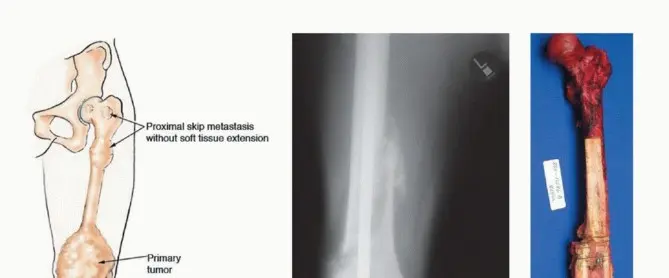

* وجود نقائل "قفزية" داخل العظم (proximal transosseous skip metastases).

* امتداد الورم بشكل كبير داخل العظم (extensive diaphyseal extension).

* وجود كتل كبيرة من الأنسجة الرخوة المجاورة، خاصة إذا كانت مصحوبة باستجابة ضعيفة للعلاج الكيميائي.